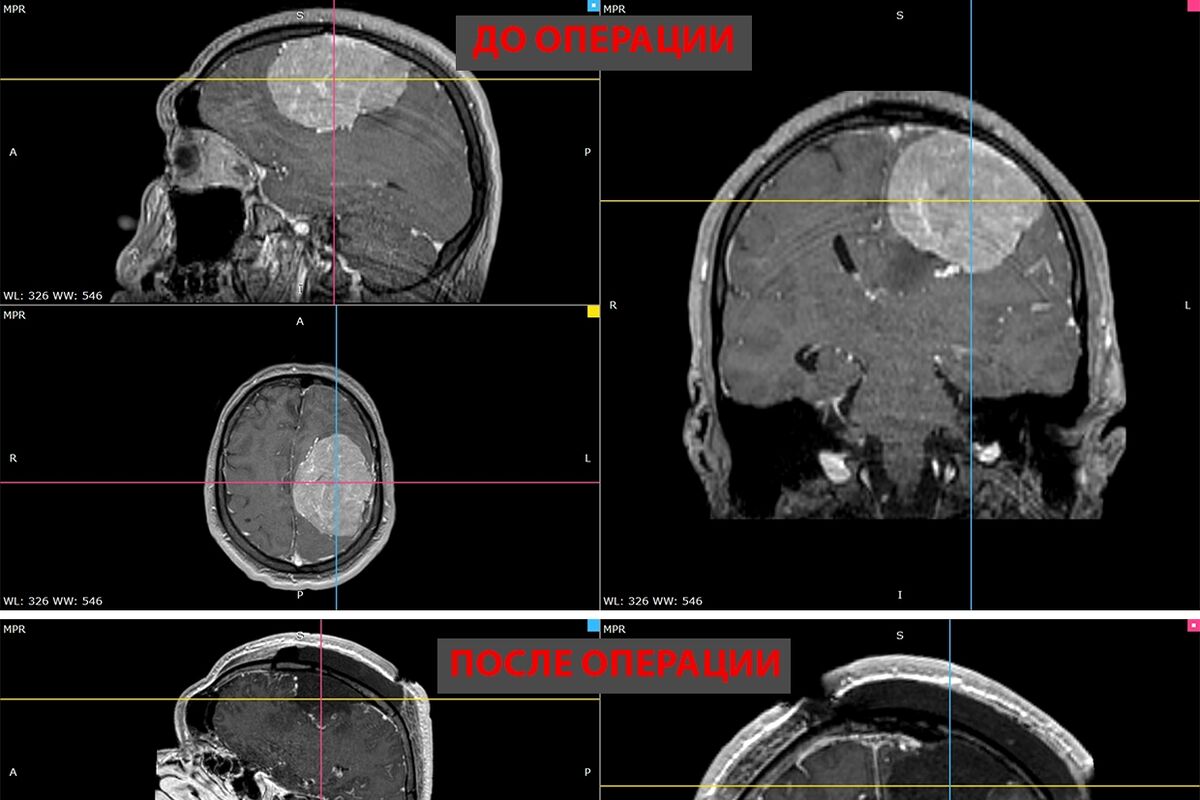

В Новосибирске врачи удалили 35-летнему пациенту гигантскую опухоль головного мозга. Об этом сообщает пресс-служба НМИЦ имени Мешалкина Минздрава России.

В ноябре прошлого года у мужчины появилась слабость в правой руке и затруднения речи — МРТ выявила у него менингиому диаметром более восьми сантиметров в левом полушарии мозга. К концу года рука практически перестала работать, ходьба давалась пациенту с трудом.

Пятичасовая операция прошла успешно. Опухоль удалили полностью. Уже на следующий день появились движения в руке, через две недели пациент снова стал сам ходить. У него восстановились речь и движения, приступы исчезли.